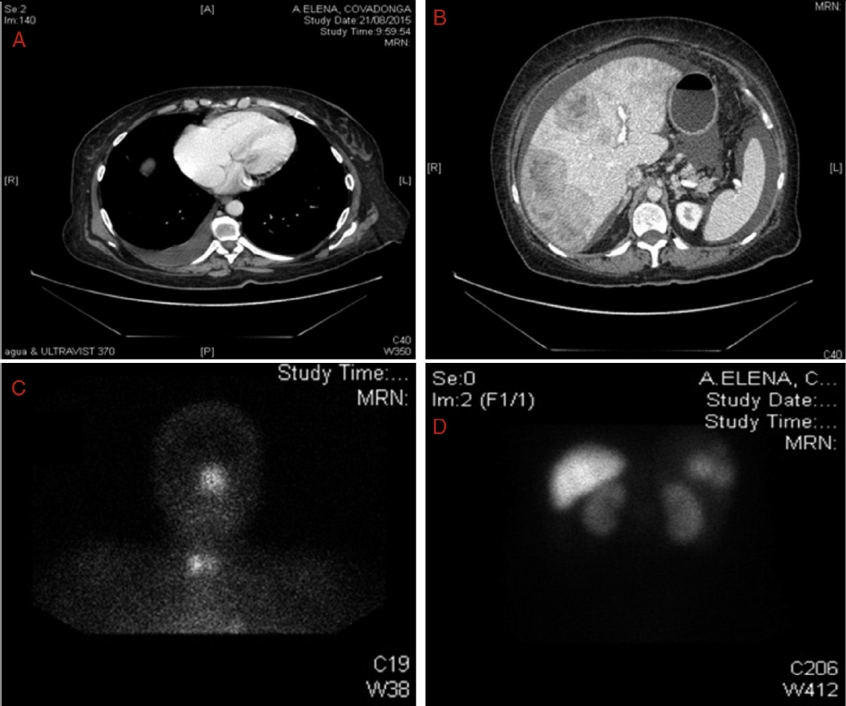

Dada la afectación polivalvular y el cuadro serotoninérgico, se sospecha SC, por lo que se realiza tomografía axial computarizada en la que se detectan imágenes compatibles con metástasis hepáticas múltiples, la mayor de 6.7 × 5 cm (Fig. 2B) con ascitis. Se realiza octreoscan (Figs. 2 C y D, donde destacan focos hipercaptantes patológicos asociados a lesiones con sobreexpresión de receptores de somatostatina en hígado (Fig. 2D), adenopatías hiliares pulmonares, derrame pleural derecho y lóbulo tiroideo derecho. En el perfil analítico correspondiente destacaba leucocitos: 12,590/ul (neutrófilos: 9.72%, linfocitos: 1.94%). Velocidad de sedimentación globular 7 mm/h (0), GGT 148/ul (7-32), fosfatasa alcalina 130/ul (35-104), lactato deshidrogenasa 364/ul (135-214), serotonina 888 ng/ml (40-200), gastrina 591 (0-100), metanefrinas en plasma y orina normales. 5-hidroxiindolacético 1895 mmol en orina de 24 h (0-50). Marcadores tumorales: antígeno CA-125 1177.8/ul (< 35); B-2 microglobulina 3.84/ul (0.8-2.3), cromogranina A 586 ng/ml (0-100).

Figura 2 A-B: Imagen de tomografía computarizada. Figura 2A: a nivel de tórax con derrame pleural derecho. Figura 2B: a nivel abdominal, hígado con múltiples imágenes de metástasis y ascitis. Figuras 2 C-D: imagen de octreoscan en el que se evidencia captación patológica en cornete nasal izquierdo y lóbulo tiroideo derecho. Figura 2C: adenopatías hiliares pulmonares. Figura 2D: focos hipercaptantes asociados a sobreexpresión de receptores de somatostatina en hígado.